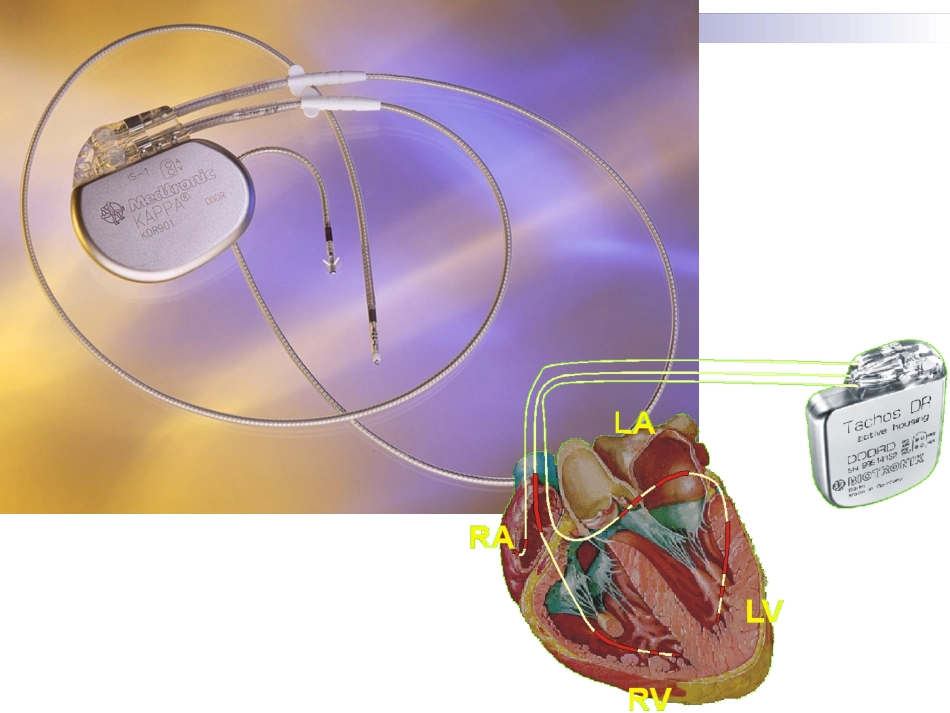

心脏起搏器心脏起搏定义人工心脏起搏(artificialcardiacpacing)是通过人工心脏起搏器或程序刺激器发放人造的脉冲电流刺激心脏,以带动心脏搏动的治疗方法。主要用于治疗缓慢心律失常,也用于快速的心律失常和治疗。什么是心脏起搏器?心脏起搏器由脉冲发生器、导线和电极组成。脉冲发生器呈扁圆形,体积非常小,大约有40506毫米,重量约30克。它实际上是一个微型计算机,由高性能电池提供能量。起搏器通常埋植在上胸部的皮下,它的导线通过静脉到达心脏,导线顶端的电极固定在心脏的内侧面心肌上。起搏器工作时,脉冲发生器发出的电脉冲,经导线、电极传到心肌,心肌感受到电脉冲刺激产生收缩。同时,起搏器电极也将心脏的电活动收集起来存入脉冲发生器内的芯片内,以便进行分析。人工心脏起搏器工作原理:监测心电、电激心脏临床上广泛应用的人工心脏起搏:就是用低能量电脉冲暂时或长期地刺激心脏,使之发生激动,以治疗严重心动过缓,心脏起搏也可用以终止或控制室上性和室性快速心律失常,称为抗心动过速起搏。心脏起博器的功能能替代或补充正常激发和控制心脏收缩的生理电子系统。它通过周期性发放的电脉冲刺激心脏,引起心搏,并实现生物机能控制。n如果心脏原有的起搏点丧失其作用而使冲动形成受扰,或者心脏固有的传导系统不能正常工作(如窦性停止、窦房阻滞、窦性心动过缓或某心房、心室出现异使节律,以及心动过速等),起搏器能帮助心脏恢复、接近正常功能。特别是对那些药物疗效不佳,甚至于治疗无效的心脏病患者,人工心脏起搏器在临床上获得了成功。绝大多数起搏器具有四个功能刺激心脏使它除极感知心脏自身电活动对增加的新陈代谢需求作出反应,提供频率适应性起搏提供由起搏器存储起来的心电诊断信息心脏起搏器的临床应用长期起搏房室传导阻滞三束支阻滞伴心脑综合症病态窦房结综合症临时性起搏指心脏病变可望恢复,紧急情况下保护性应用和诊断应用的短时间使用心脏起搏诊断:还可用于某些疾病的诊断。例如心房调搏辅助诊断可疑的冠心病、心房超速起搏法诊断窦房结功能不全,预测完全性房室传导阻滞患者是否有发生心脑综合症的危险等。药理及实验研究:人工心脏起搏技术在心血管的生理和病理生理以及药理和临床应用的实验研究工作中,也取得了发展。例如在心律失常方面,将逐步揭示一些我们还不能解释的电生理现象,对心律失常的诊断和治疗会起到更积极的作用。永久性与临时性心脏起搏器埋藏于体内的起搏器为埋藏式起搏器,作为永久性心脏起搏,用于慢性或间歇发作的严重缓慢性心律失常如心脏传导阻滞、病态窦房结综合征等;放在体外的起搏器为体外起搏器,用于临时性起搏,如永久性起搏器植入的过渡或心脏骤停的抢救等等。临时起搏的适应征1.急性前壁心肌梗塞伴有Ⅲ度或高度房室传导阻滞,或下壁梗塞伴有Ⅲ度或高度房室传导阻滞经药物治疗无效者。2.急性心肌炎或心肌病伴有阿斯综合征者3.药物中毒引起的心动过缓,并发阿斯综合征者.4.心脏手术后发生的Ⅲ度房室传导阻滞者5.电解质紊乱,如高血钾引起的Ⅲ度房室传导阻滞者。6.超速起搏用以诊断及治疗其他方法所不能解决的室上速或室性心动过速。7.保护性应用于更换永久起搏导管前,冠脉造影,电击复律,外科手术等。强干扰信号对起搏器的影响当患者处于较强的50Hz市电或高频强电磁场干扰的环境中时,如果这些干扰信号很强,频率远高于起搏频率,这些干扰信号和感知的R波一样,能使按需功能控制器的单稳态电路提前触发;脉冲发生器在干扰信号存在的时间内一直处于抑制状态,致使起搏器停止发放起搏脉冲,从而使患者失去人工心脏起搏。解决方法?解决方法保持在强干扰存在的条件下,把强干扰信号衰减,使之不能触发按需功能控制器,失去对脉冲发生器的抑制作用,脉冲发生器按自己固有频率发放起搏脉冲,起博器转换为固定式工作,其起搏频率稍快于按需型(这是扣除按需型的反拗期的结果)。强干扰一旦消失,起搏器又能自动恢复到按需工作状态。具体如何实现?最高起搏频率限制电路患者安装起搏器后的心率多数是依赖起搏器的工作频率,如果起搏器因电源、元器件变质或损坏而造...